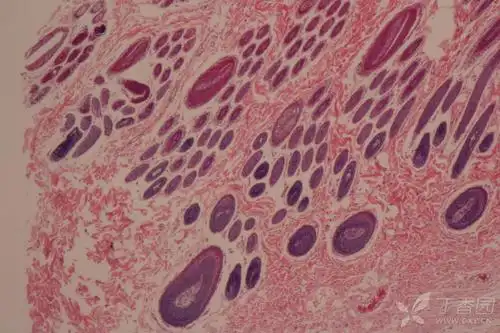

请教皮肤切片he染色附属器辨认,谢谢